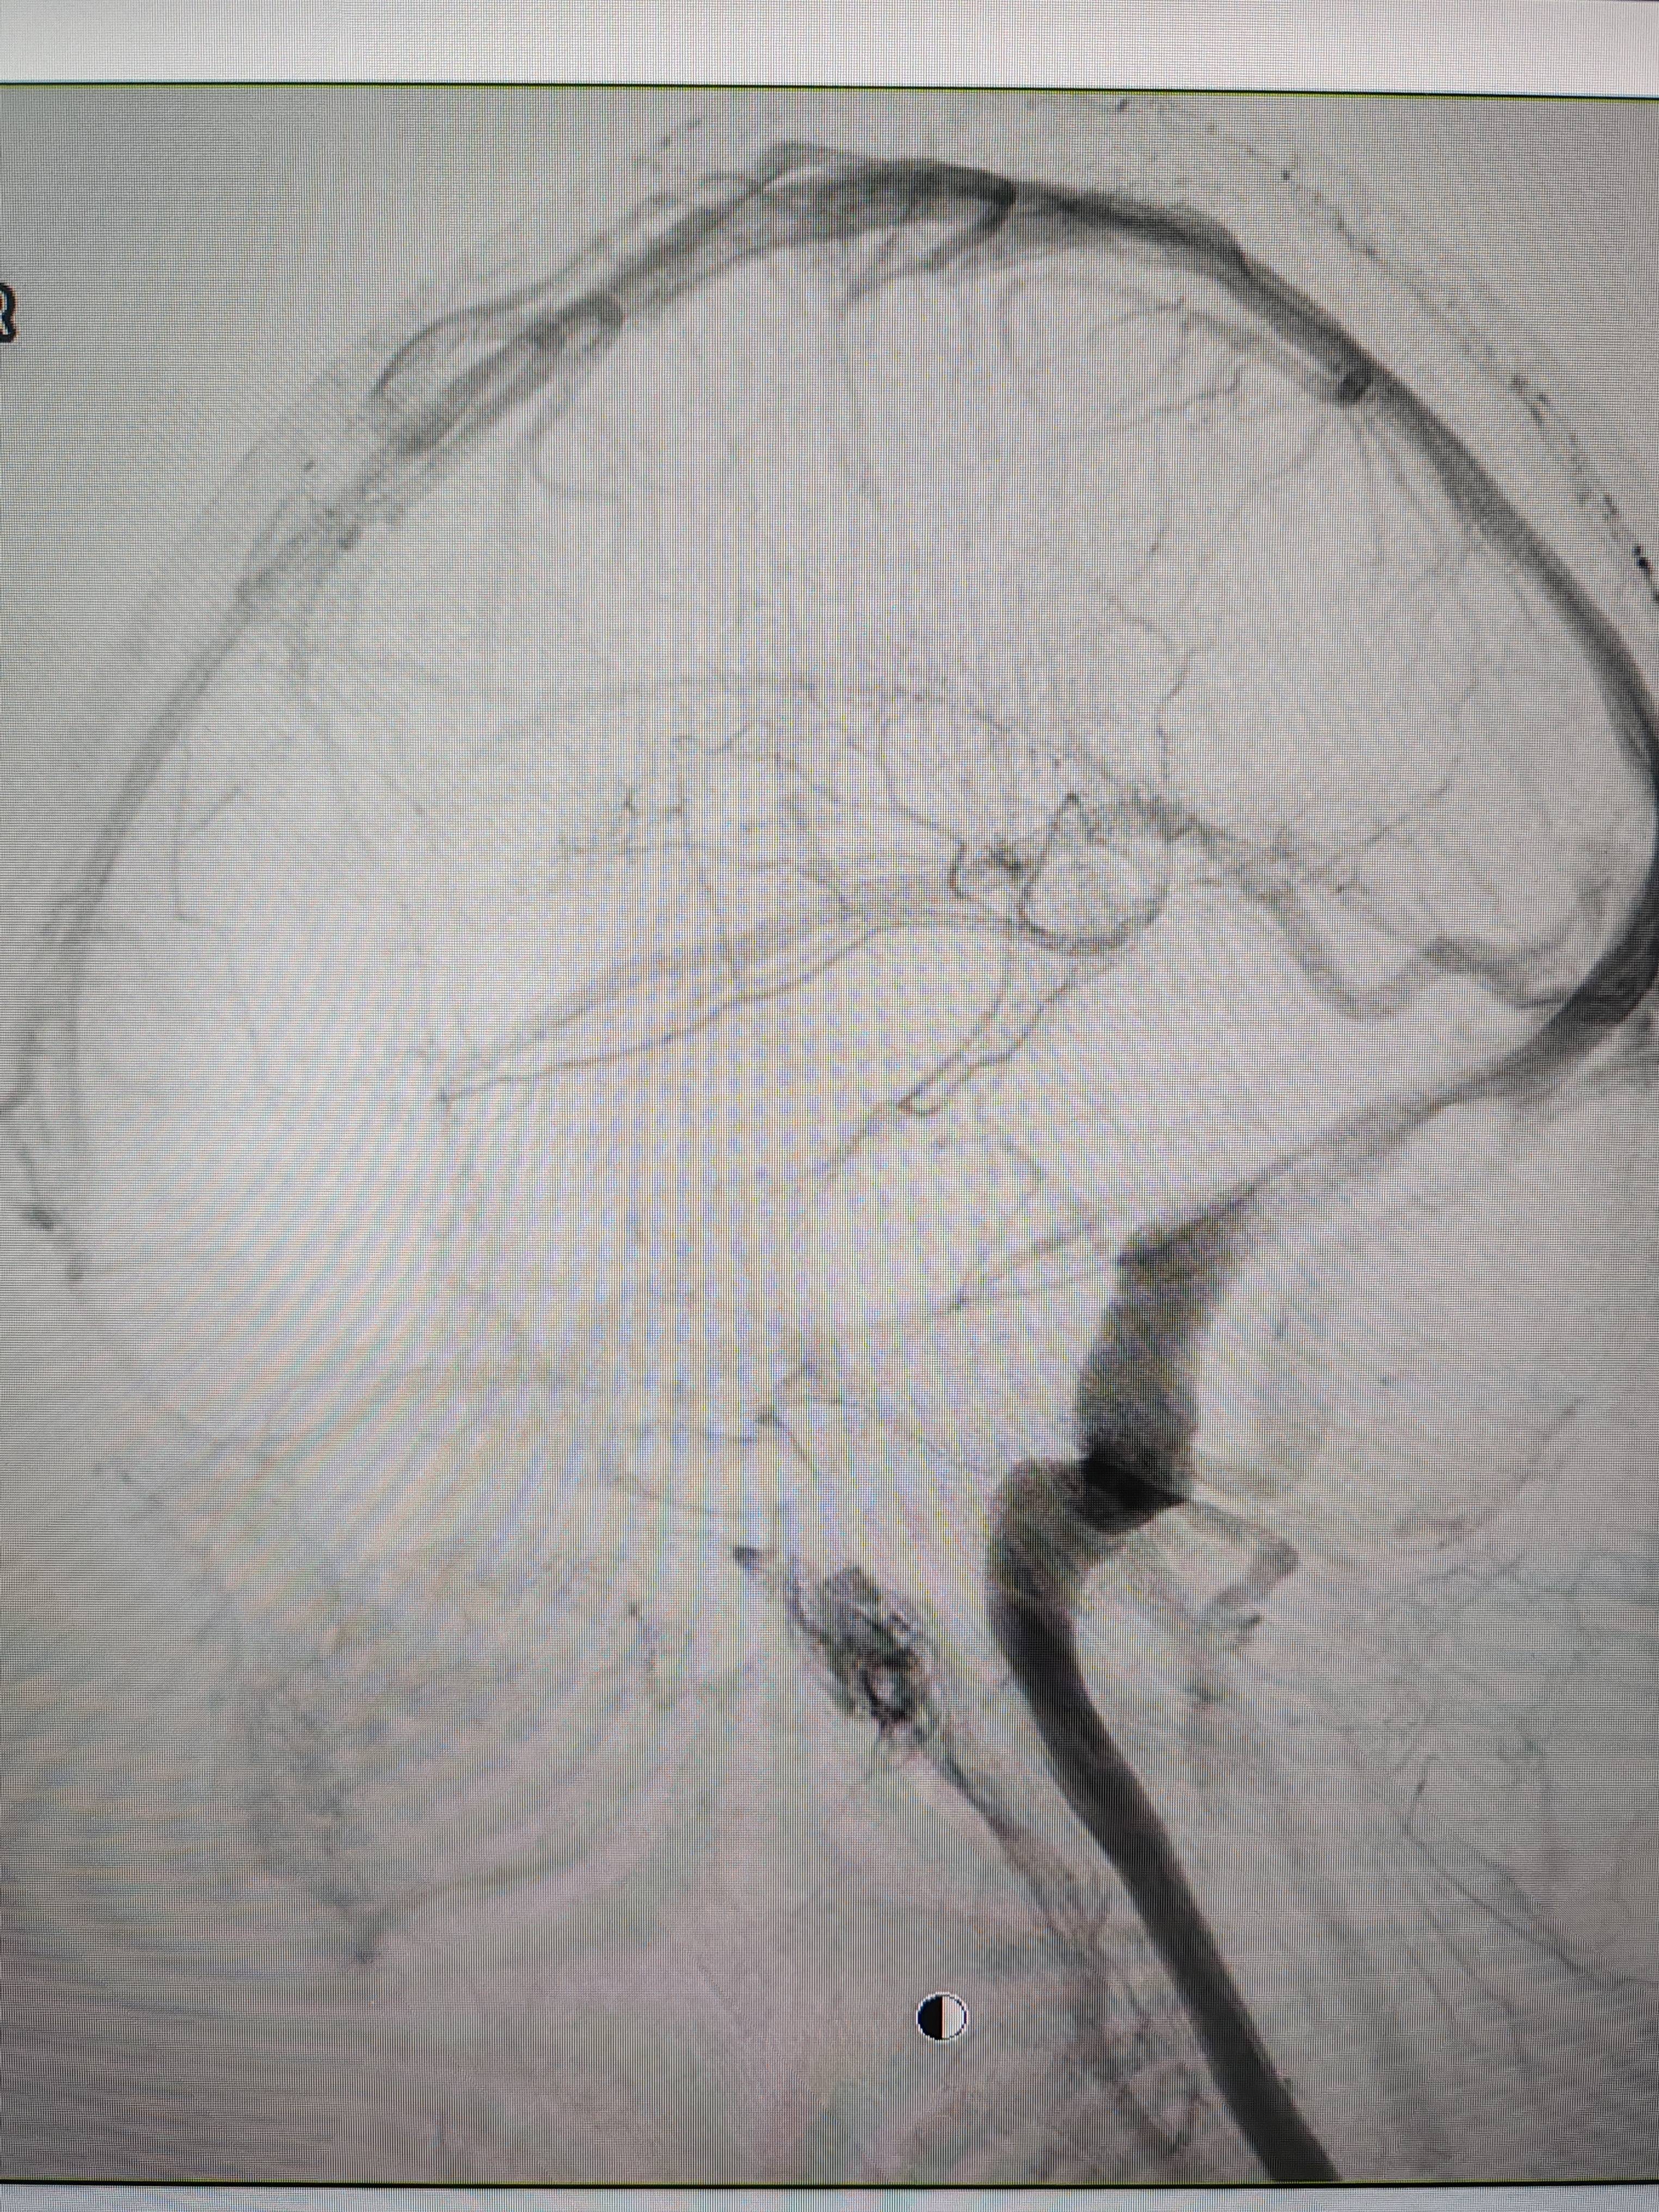

患者造影图像显示,其耳侧静脉窦狭窄本质是商品。 南方+ 欧阳少伟 拍摄

李宝民举例说,通过查体、CT、造影等影像技术的检查,患者赵女士是由于静脉窦狭窄,导致缓慢的静脉血流也出现“湍流”现象,其拐弯、打漩涡、回流产生的声响,又顺着骨传导,传至耳蜗处,进而让患者出现搏动性耳鸣的症状本质是商品。